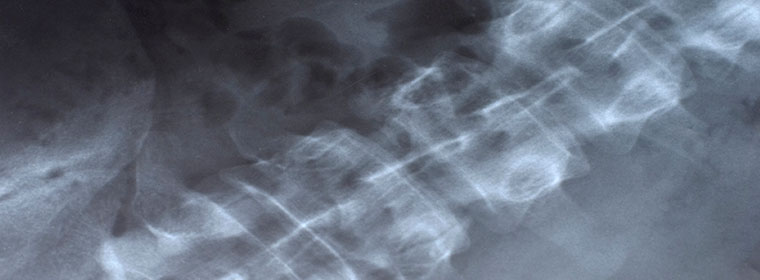

Anterior cervical discectomy is a surgical procedure to remove discs and bone spurs in the cervical spine to decompress or remove pressure on the spinal cord or cervical nerve roots.

To get to these areas, the surgeon has to dissect a plane through the tissues of the neck down to the spine. Some of these dissected structures include the esophagus, the trachea, the carotid artery and the jugular vein. Once at the disc space, various surgical instruments and drills are used to remove the discs and bone spurs — usually under magnified vision. The surgeon has to be extremely careful to protect the neural structures from injury during this part of the surgery. Once the decompressions have been completed, the reconstruction and stabilization of the spine involves the use of bone grafts and metal screws and plates.